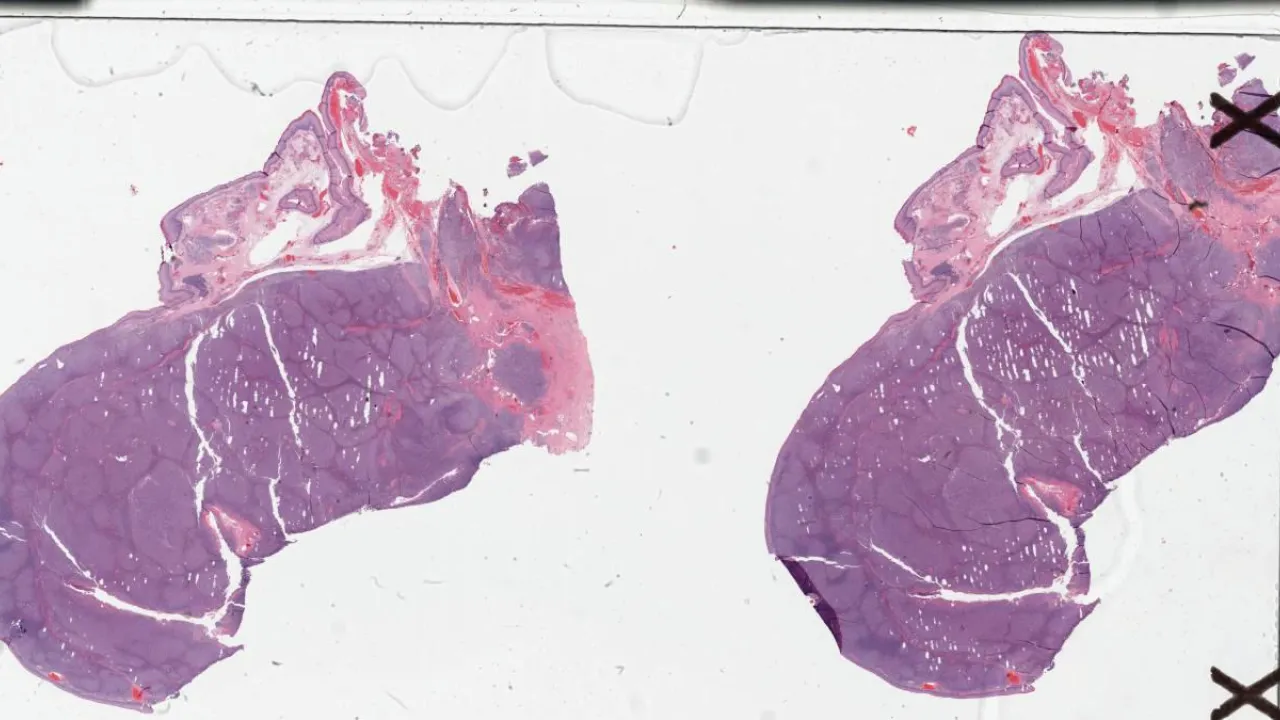

Lymph node, follicular lymphoma